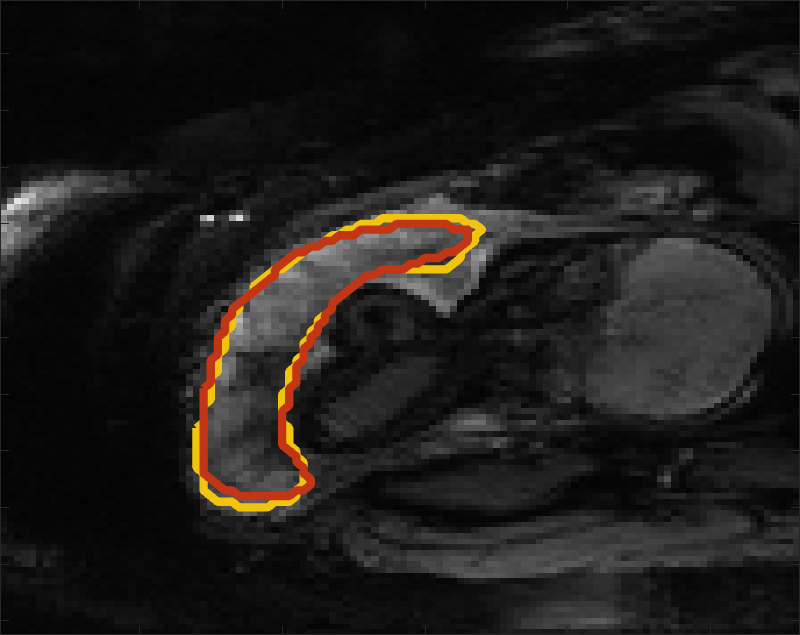

Despite its importance for many downstream clinical research tasks, placental segmentation is often performed manually and can take a significant amount of time, even for a trained expert. For BOLD MRI studies, manual segmentation is rendered more challenging due to the sheer number of MRI scans acquired and rapid signal changes due to the experimental design. Experiments acquire several hundred whole-uterus MRI scans to observe signal changes in three stages: i) normoxic (baseline), ii) hyperoxic, and iii) return to normoxic. During the hyperoxic stage, the BOLD signals increase rapidly, leading to hyperintensity throughout the placenta. Furthermore, the placental shape can undergo large deformation caused by maternal breathing, contractions, and fetal motion which can be particularly increased during hyperoxia [25]. See Fig. 1 for two examples.

Fig 3 compares the predicted label maps with ground truth on subjects with increasing Dice scores using the BW-CE model. The model accurately identifies the location of the placenta, but in the worst cases misses boundary details.